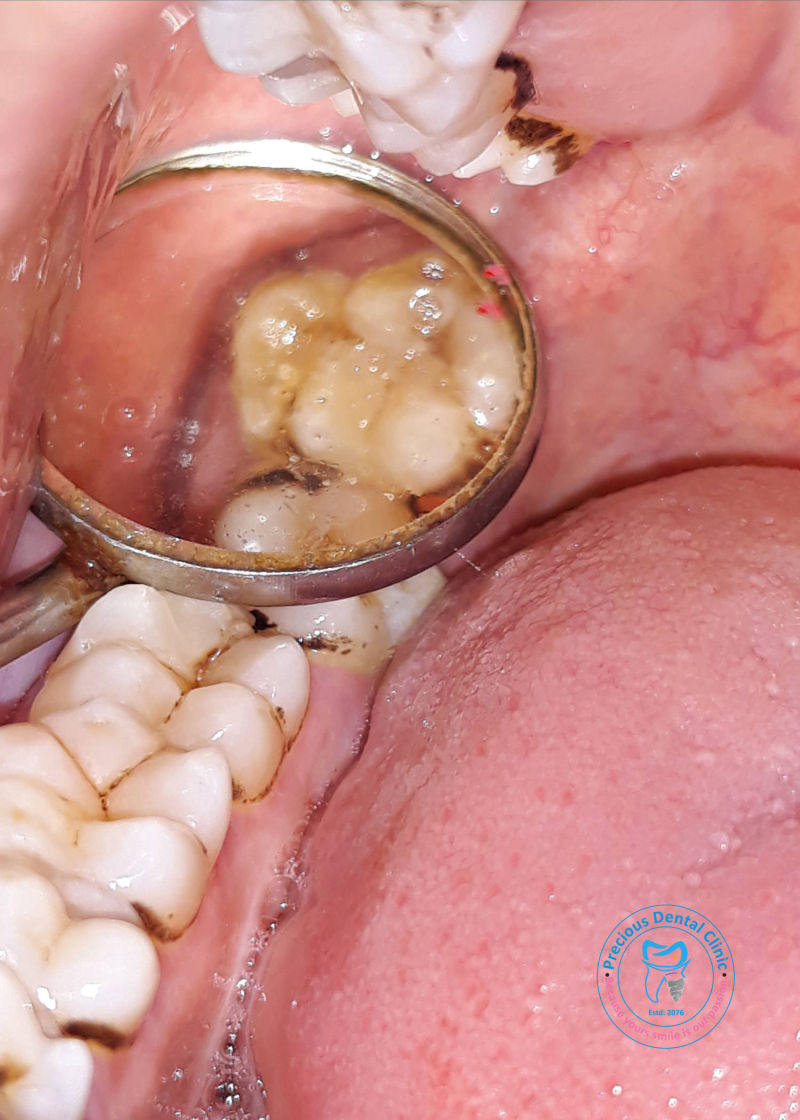

Collection of photos, here you will find the photos of doctor, services, environment and work.